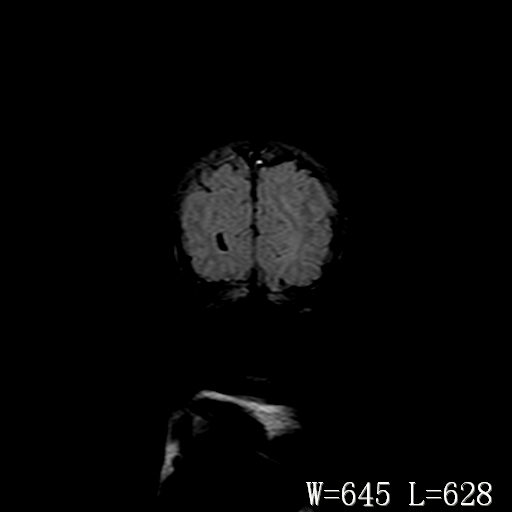

男,4天,发复抽搐1天。

脑干形态欠规则,信号增高,不知怎么解释?

脑干背侧面t1高信号是,新生儿正常已经髓鞘化好的部位